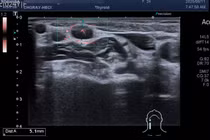

Ung thư tuyến giáp là một trong những bệnh thường gặp ở vùng đầu, mặt, cổ ở cả nam và nữ giới, bệnh thường không có dấu hiệu rõ ràng nên âm thầm di căn đến nhiều bộ phận khác, khi phát hiện bệnh đã ở giai đoạn muộn.